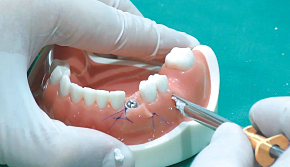

4. Bone Carrier를 터널 공간에 삽입

-

5. 터널 공간에 골이식재 주입